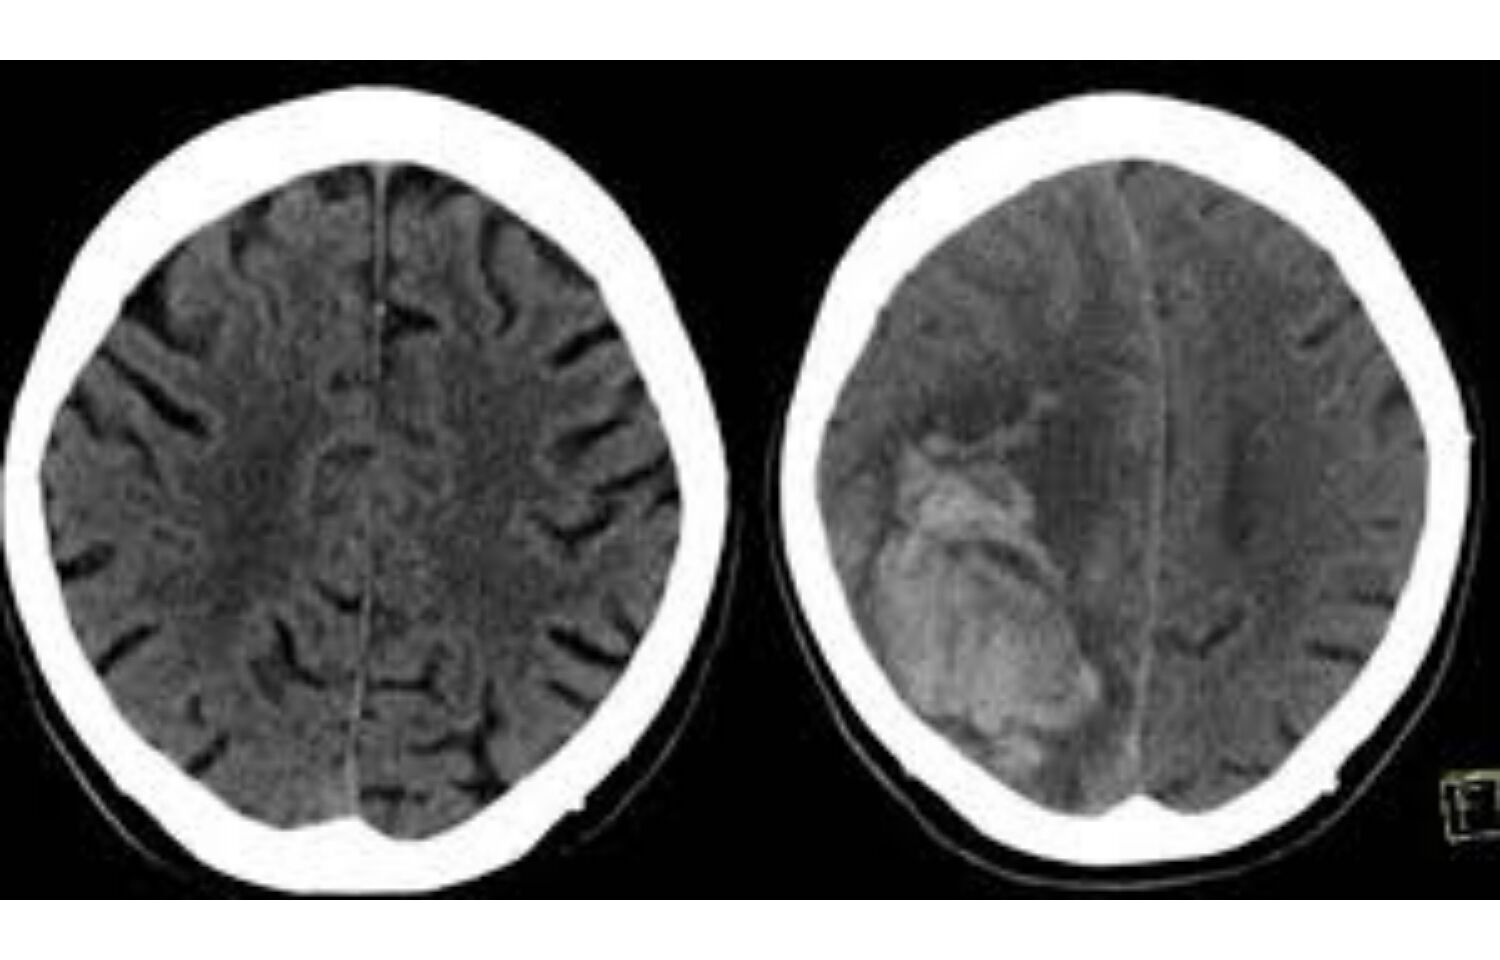

Blood Thinners Brain Bleeding . By radiological society of north america. 1 anticoagulation therapy has been proven to be efficacious in. In a delayed traumatic intracranial hemorrhage, bleeding in the brain occurs after the initial trauma, usually within 48 hours, after an initial negative head ct. The left image shows the initial ct scan of the brain. Be watchful for any warning signs of complications while taking any anticoagulants. Popular blood thinners may lead to brain bleeding after head injury. Use of blood thinners or anticoagulants: Now, new research finds that faster treatment for these patients is associated with a greater likelihood of survival. Intracranial hemorrhage is the most serious and lethal complication of oral anticoagulants (oacs). Urine that’s red or dark brown. Studies suggest that patients on blood thinners have a roughly 1% annual risk of experiencing a brain bleed. If you’re taking medications that affect blood clotting, your risk of a brain bleed.

Blood Thinners Brain Bleeding 1 anticoagulation therapy has been proven to be efficacious in. Be watchful for any warning signs of complications while taking any anticoagulants. Popular blood thinners may lead to brain bleeding after head injury. Studies suggest that patients on blood thinners have a roughly 1% annual risk of experiencing a brain bleed. In a delayed traumatic intracranial hemorrhage, bleeding in the brain occurs after the initial trauma, usually within 48 hours, after an initial negative head ct. The left image shows the initial ct scan of the brain. 1 anticoagulation therapy has been proven to be efficacious in. Use of blood thinners or anticoagulants: Now, new research finds that faster treatment for these patients is associated with a greater likelihood of survival. By radiological society of north america. If you’re taking medications that affect blood clotting, your risk of a brain bleed. Urine that’s red or dark brown. Intracranial hemorrhage is the most serious and lethal complication of oral anticoagulants (oacs).

Association between blood thinners usage and intracranial bleeding in Blood Thinners Brain Bleeding Intracranial hemorrhage is the most serious and lethal complication of oral anticoagulants (oacs). The left image shows the initial ct scan of the brain. Studies suggest that patients on blood thinners have a roughly 1% annual risk of experiencing a brain bleed. Now, new research finds that faster treatment for these patients is associated with a greater likelihood of survival.. Blood Thinners Brain Bleeding.

Popular blood thinners may lead to brain bleeding after head injury Blood Thinners Brain Bleeding Use of blood thinners or anticoagulants: The left image shows the initial ct scan of the brain. In a delayed traumatic intracranial hemorrhage, bleeding in the brain occurs after the initial trauma, usually within 48 hours, after an initial negative head ct. Urine that’s red or dark brown. Intracranial hemorrhage is the most serious and lethal complication of oral anticoagulants. Blood Thinners Brain Bleeding.

Study shows common blood thinners link to brain bleeds Blood Thinners Brain Bleeding Intracranial hemorrhage is the most serious and lethal complication of oral anticoagulants (oacs). The left image shows the initial ct scan of the brain. Studies suggest that patients on blood thinners have a roughly 1% annual risk of experiencing a brain bleed. If you’re taking medications that affect blood clotting, your risk of a brain bleed. Now, new research finds. Blood Thinners Brain Bleeding.

CT scan of the brain of a 73 year old man show intracranial bleeding Blood Thinners Brain Bleeding Intracranial hemorrhage is the most serious and lethal complication of oral anticoagulants (oacs). Urine that’s red or dark brown. If you’re taking medications that affect blood clotting, your risk of a brain bleed. Now, new research finds that faster treatment for these patients is associated with a greater likelihood of survival. The left image shows the initial ct scan of. Blood Thinners Brain Bleeding.

Popular Blood Thinners May Lead to Brain Bleeding after Head Injury Blood Thinners Brain Bleeding The left image shows the initial ct scan of the brain. In a delayed traumatic intracranial hemorrhage, bleeding in the brain occurs after the initial trauma, usually within 48 hours, after an initial negative head ct. Be watchful for any warning signs of complications while taking any anticoagulants. By radiological society of north america. Use of blood thinners or anticoagulants:. Blood Thinners Brain Bleeding.